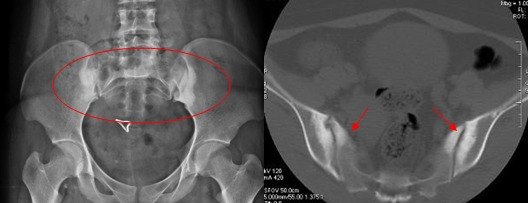

如何在ct上区分骶髂关节退变强直致密性髂骨炎

图片尺寸640x475